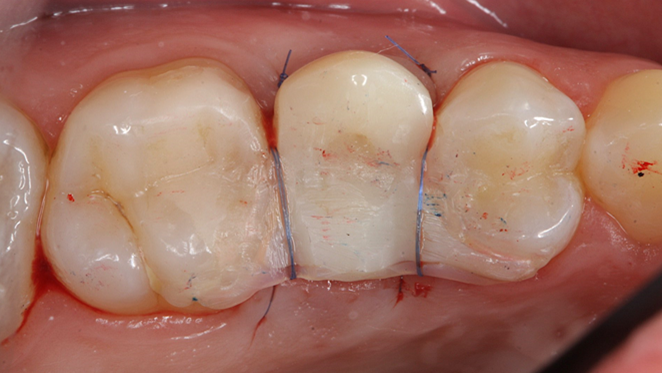

Clinical case: Digital Data Save concept in upper jaw premolar area

- Courtesy of Dr. Lysov Alexander Dmitrievich & Dr. Sofronov Matvey Vitalievich, Russia -

AnyRidge, R2GATE, R2GATE guide, ISQ value, initial stability, immediate loading, KnifeThread, maxillary posterior, #14, Digital, Dr. Lysov Alexander Dmitrievich, Dr. Sofronov Matvey Vitalievich, zirconia abutment, CAD/CAM crown

“AnyRidge & R2GATE show stable results

after immediate extraction, immediate implant placement, & immediate loading,

even with low bone density.”